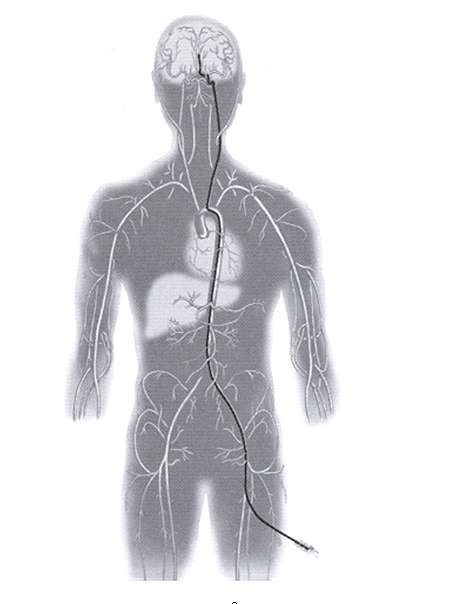

Embolization is a procedure to block abnormal blood vessels in the nidus of the AVM. In other words, the shunts in the nidus are blocked one by one during the embolization procedure. This is an angiogram based procedure and not a surgical procedure. It is referred to as a minimally invasive procedure, as unlike surgery, no cutting in the head or skull or manipulation of the brain is involved. Instead, a small plastic tube called a catheter is introduced into the femoral artery in the upper thigh/groin area (Figure 4). From this artery the catheter is carefully navigated into the brain and specifically into the arteries in the brain that are the shunts of the AVM. Then these shunts are occluded by injection through this catheter of agents that block the blood vessels. These shunts are abnormal blood vessels that do not supply normal brain and simply serve as a conduit between the artery and the vein and therefore their blockage will not be of any consequence in the patient.

Figure 4. Embolization procedure is performed by introducing a small catheter through the artery in the groin area and carefully navigating the catheter into the brain arteries. Once in the brain arteries, then the tip of the catheter is carefully placed into the individual shunts of the AVM and one by one they are blocked by introduction of a blocking agent into these shunts. This blocking agent is injected through the catheter.